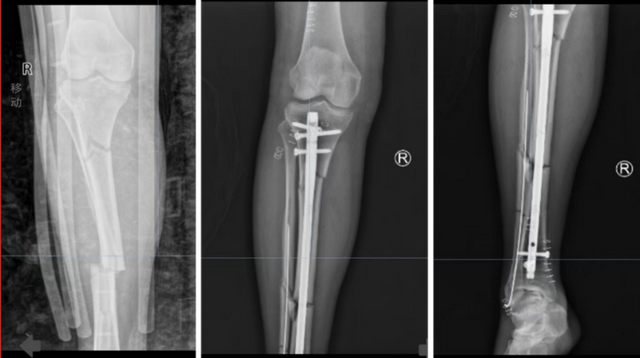

胫腓骨多端骨折胫骨髓内钉+腓骨弹性髓内钉固定